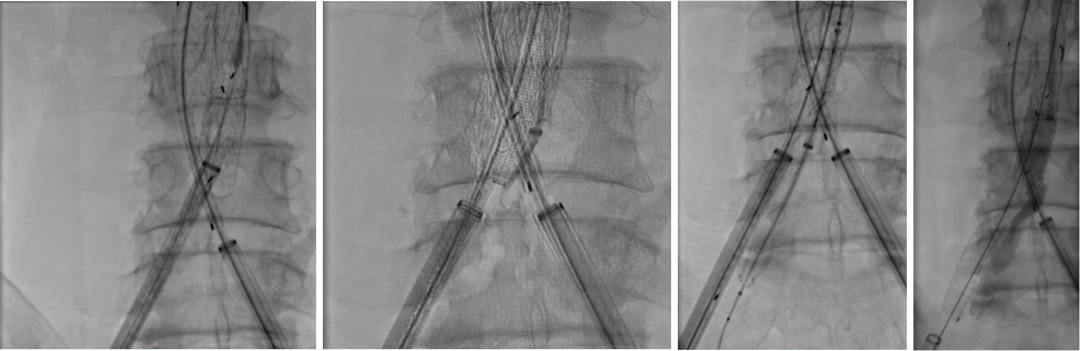

自制内分支,保留双侧髂内动脉,预置牵张导丝,方便重建

肾下引入腹主支架后,髂支引入改装后的内分支,利用牵张导丝,引导长鞘进入分支,超选重建髂内